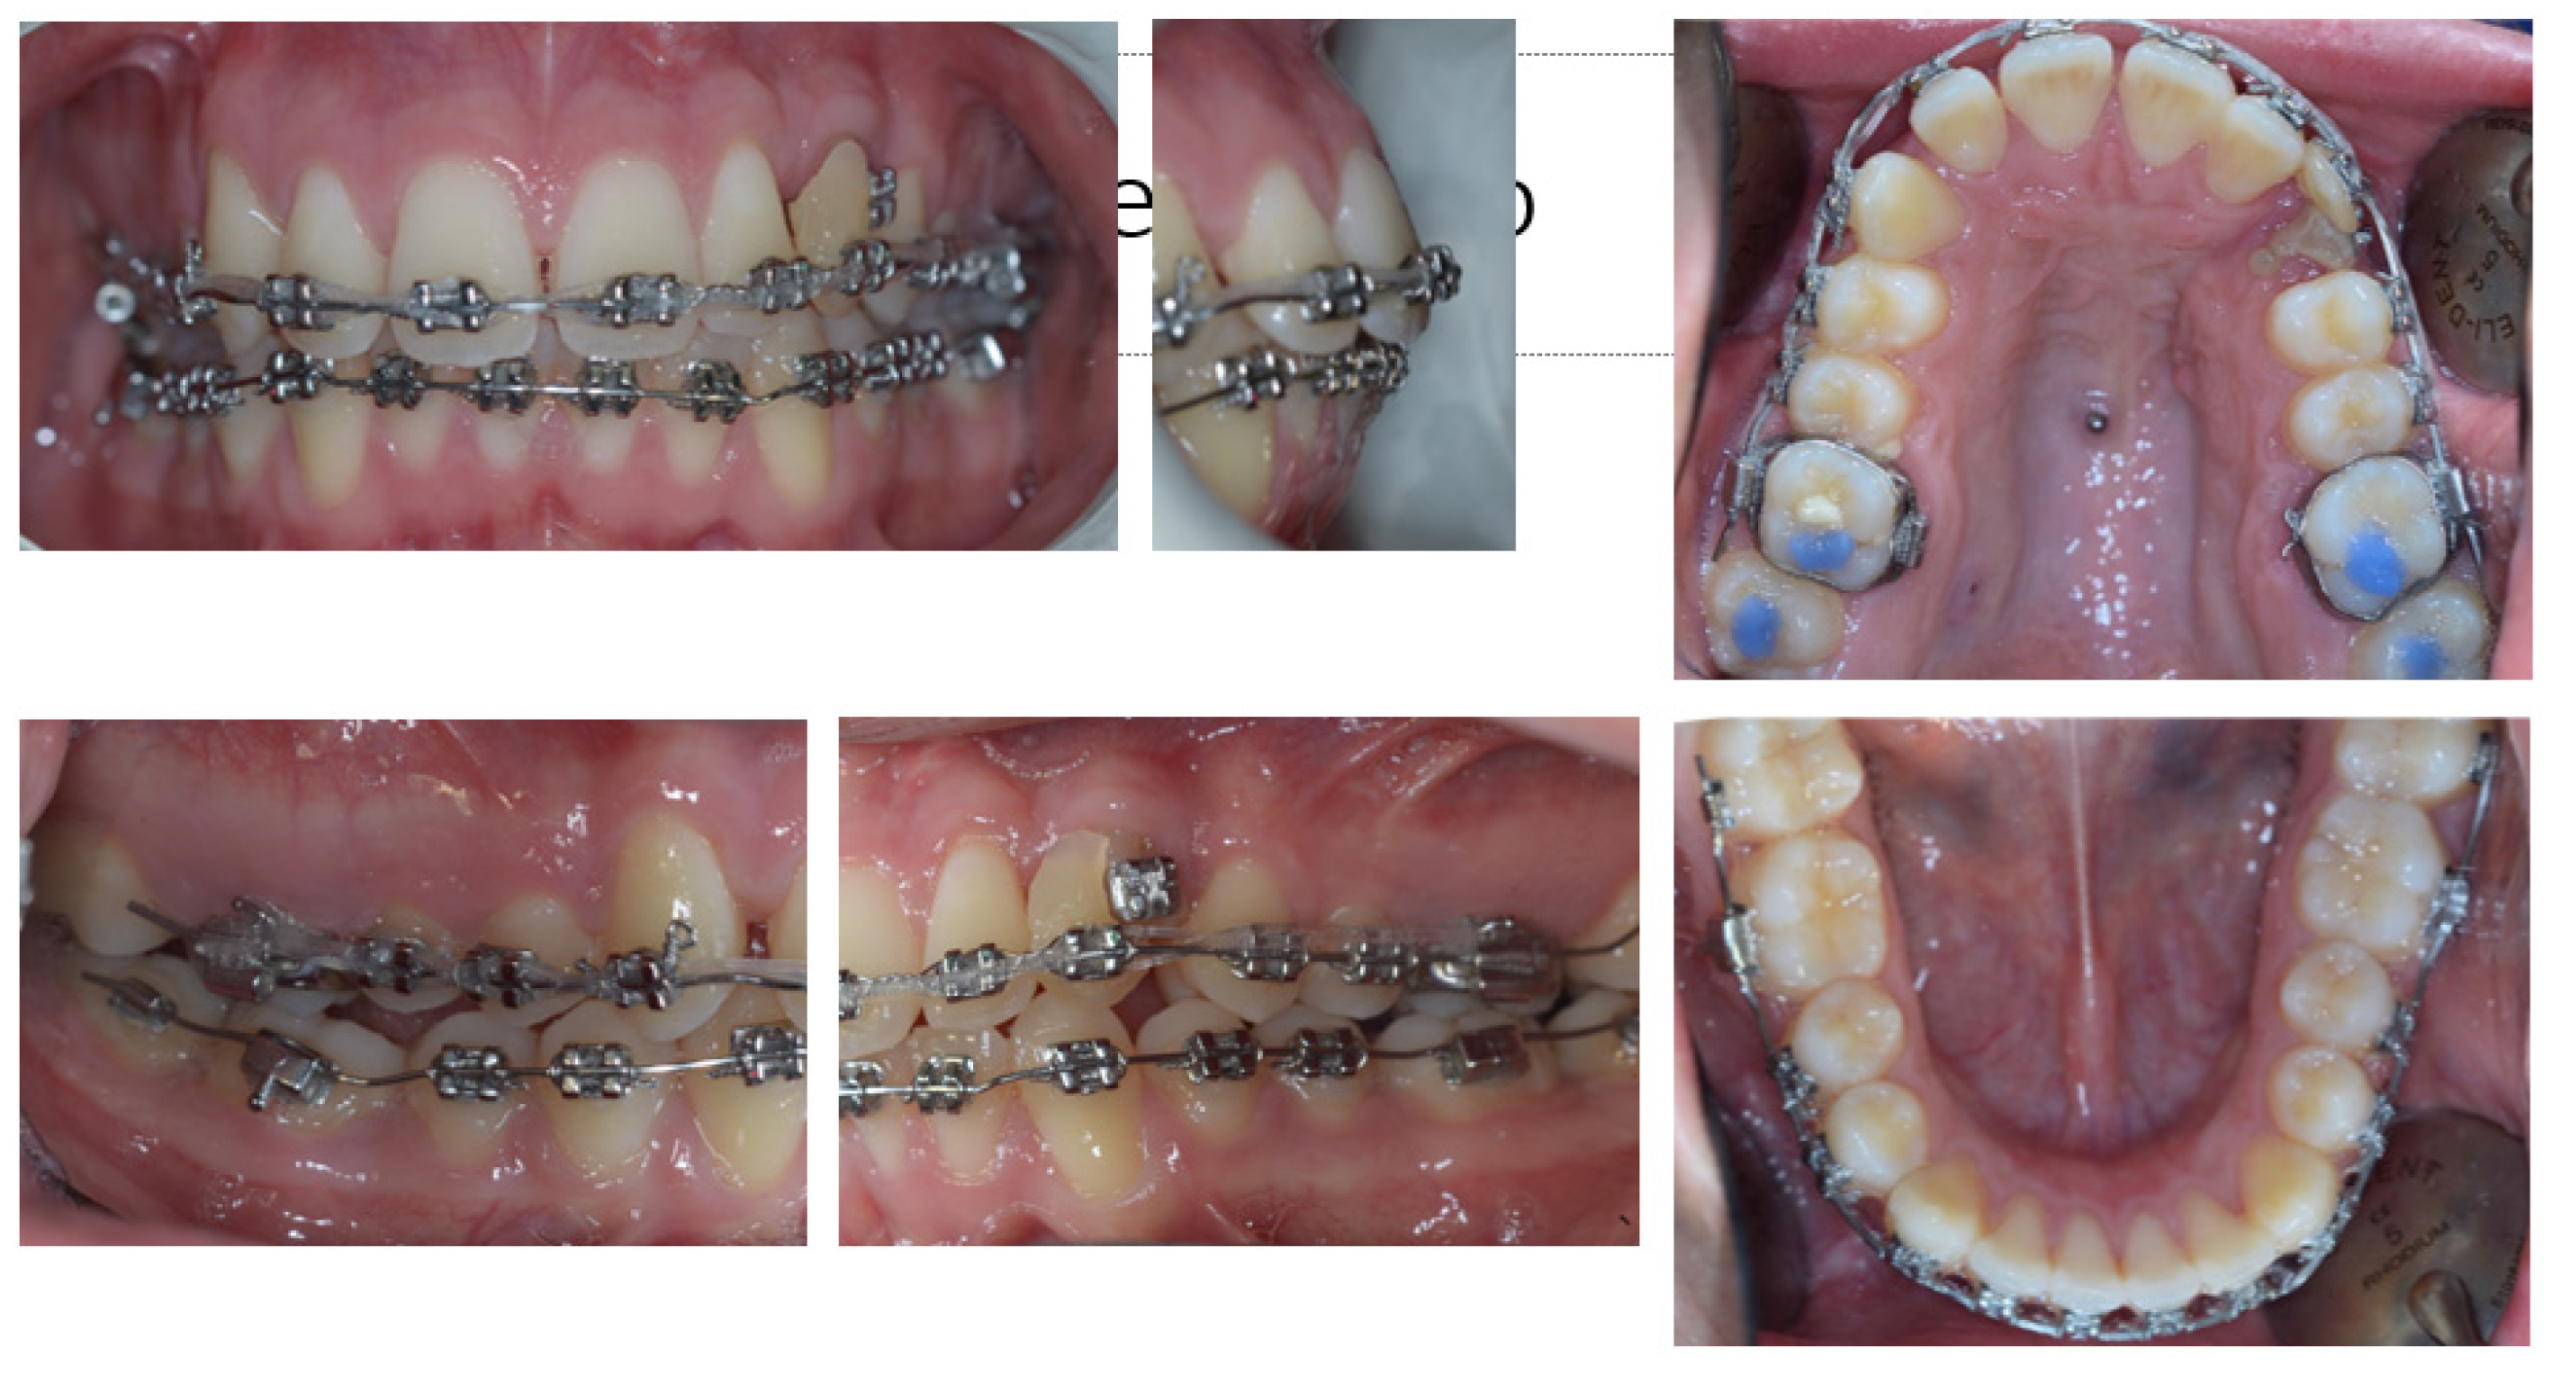

3. Therapeutic Interventions

4. Follow-Up and Outcomes